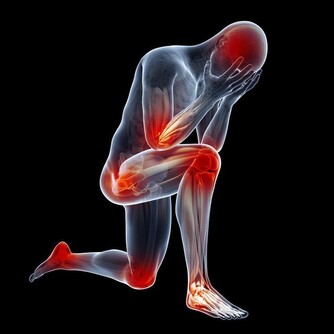

相信大家都不想痛風發作,不僅是因為那滋味太痛苦了,還因為它會帶來各種並發症,比如說關節疼痛,嚴重的甚至會變形,不能正常活動關節。若是尿酸結晶沉積在腎小管裡,還有可能損傷腎臟,形成結石,給身體加上另一重痛苦。